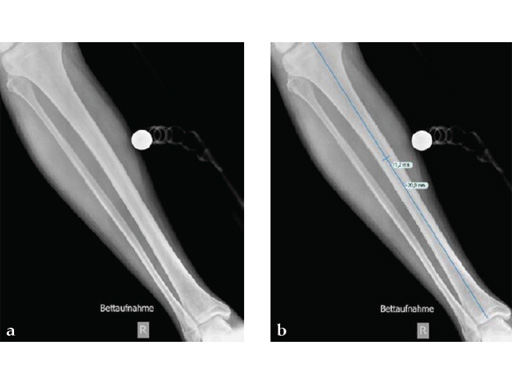

Case 1: A 33-year-old man with a third degree open fracture of his left tibia was initially treated with an external fixator and unilateral compartment release. He had undergone ACL reconstruction in the past.